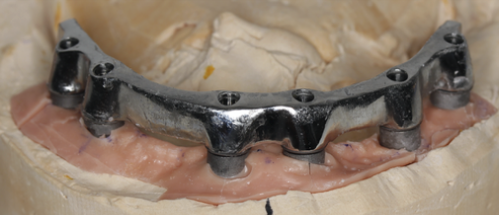

Mai întâi se realizează bara (Fig. 3.9.10) peste care se va aplica viitoarea lucrare. Apoi se realizează o machetă a lucrării pentru a analiza corectitudinea ocluziei (mușcăturii) (Fig. 3.9.11) precum și înălțimea dinților și aspectul facial al pacientului (Fig. 3.9.12, și Fig. 3.9.13).